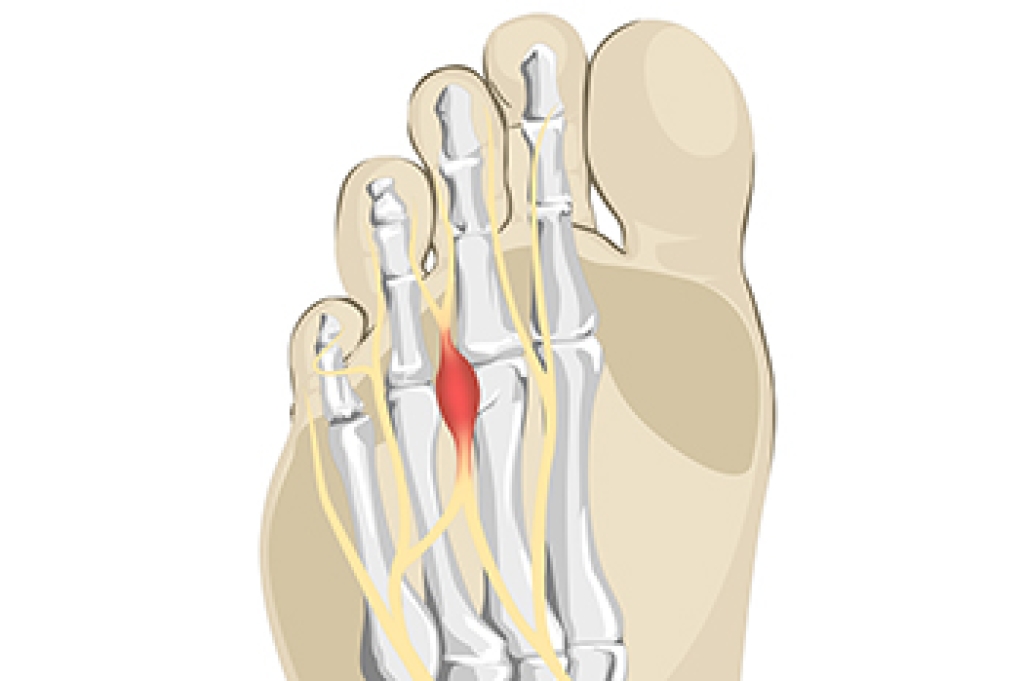

The feet are typically affected with the condition that is known as peripheral neuropathy. It causes the inability to feel sensations on the feet, and existing cuts, bruises, and scrapes may go unnoticed. There are various categories of specific types of nerves, consisting of sensory, motor, and autonomic nerves. Pain and touch are products of the sensory nerves, while the motor nerves control the muscles. Automatic functions of the body come from the autonomic nerves, and bladder function and blood pressure fall into this area. The symptoms that many people experience with neuropathy can include a loss of balance, weakness in the feet, in addition to a tingling or numbing sensation in the hands and feet. Diabetic patients may be prone to developing neuropathy, and infected cuts on the feet may go unnoticed, possibly leading to serious complications. If you have any symptoms that may indicate neuropathy, it is suggested that you consult with a podiatrist who can help you to manage this condition.

Neuropathy is a condition that leads to damage to the nerves in the body. Peripheral neuropathy, or neuropathy that affects your peripheral nervous system, usually occurs in the feet. Neuropathy can be triggered by a number of different causes. Such causes include diabetes, infections, cancers, disorders, and toxic substances.

Those with diabetes are at serious risk due to being unable to feel an ulcer on their feet. Diabetics usually also suffer from poor blood circulation. This can lead to the wound not healing, infections occurring, and the limb may have to be amputated.